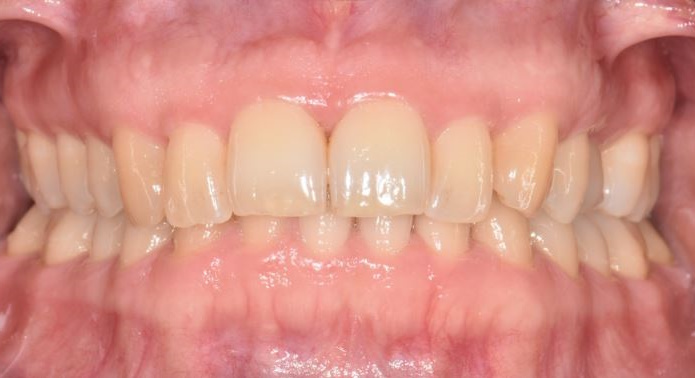

Periodontal health

The clinical presentation and diagnostic criteria that indicate a diagnosis of periodontal health are:

Clinical presentation:

- No visible interdental recession or bone loss.

- Minimal or absent gingival inflammation, gingival tissues stippled.

- No increase in probing pocket depth beyond 3.5 mm.

- Patient may or may not have good plaque biofilm control.

Diagnostic criteria:

- No sites with bone loss >2 mm from cemento-enamel junction due to periodontitis.

- Bleeding on probing at <10% sites.

- Probing pocket depth less than or equal to 3.5 mm